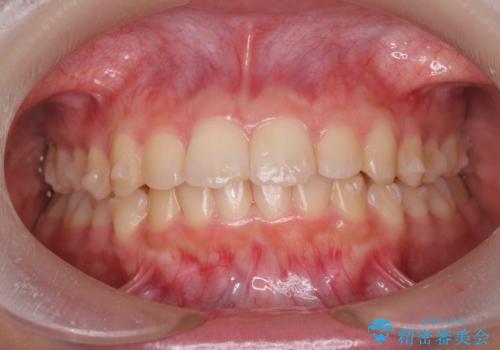

- 突出感のある、前歯の矯正治療を求めて来院されました。

軽度な突出・ガタつきを26枚・約半年の矯正治療期間で計画するインビザラインモデレートプランで治療を始めて行きます。

約半年といった短期間で、前歯の角度やガタつきを改善することができました。